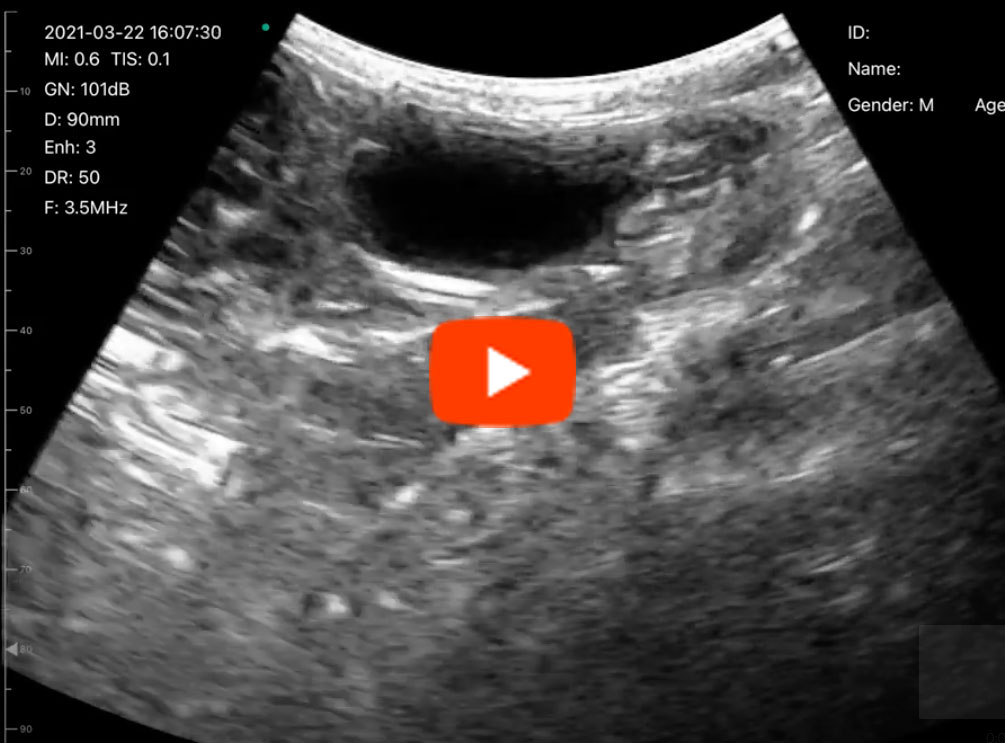

C6C胆嚢1

C6C胆嚢2

C6C動画1

C6C動画2

C6C動画3

C6C動画4